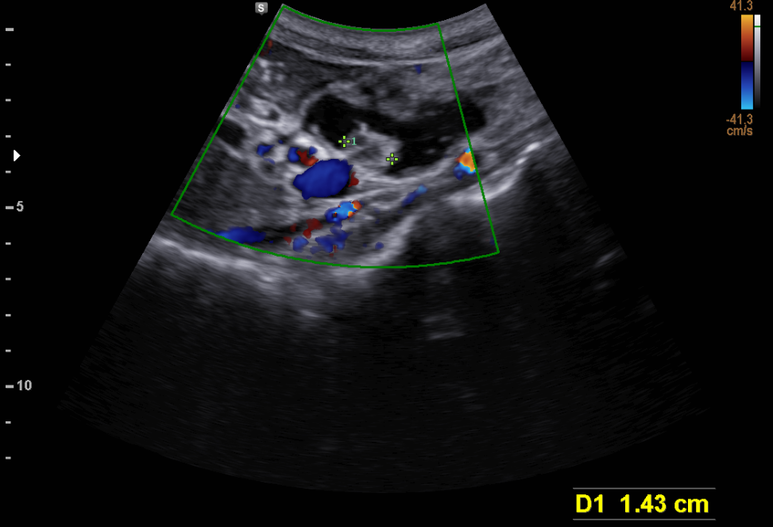

상기 환자 초음파 시행

체부 췌도가 13 mm까지 확장

미부도 확장 확인

췌두부의 췌도 확장과 결절 소견

IPMN, main duct type, 췌관내 유두상 점액 종양, 주췌관형으로 MRCP/ERCP등 검사 후 수술적 치료 상의 위해 의뢰함.